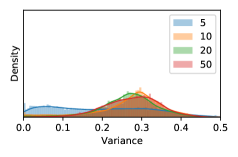

To model how different classifiers will respond to a given input , we assume that the prediction from classifier is sampled from a beta distribution that is characterized by two parameters by and . We further assume that is fixed to the same constant value for all ’s. Under this assumption, each input can be described by ( can be calculated since is fixed), easing further analysis. The Severity Level (SL) of the case represented by image can be characterized by the parameter . The larger the value of , the more severe the case of is. When and are close, the case is ambiguous as the distribution shifts towards being symmetric (i.e. signifying much disagreement among classifiers) rather than being one-sided (i.e. consensus among classifiers that is negative or positive). We provide a set of examples in Figure 2 and also Figure S.8 in the supplementary materials showing how the beta distribution can be used to capture diverse predictions given by an ensemble learner.

In contrast, the MC-dropout method showed the worst overall performance among the three, as it can be seen from the high ratios of SL0 examples among the uncertain negatives in Figure 4. The histograms in Figure 2 provides another perspective to look into the phenomenon, where a decent proportion of MC-dropout model’s predictions on SL0 inputs entailed low confidence (far from 0 or 1), which from another angle explained why MC-dropout was less specific in terms of lower FNP; many no-DR inputs (i.e. SL0) were erroneously assigned high uncertainty by MC-dropout models.

As discussed in Section 5.1 and Section 5.3 in the main paper, the mean metric and the stacking ensemble will have better performance in the precision (specificity) on the ambiguous data. Here, more detailed results are shown in Figures S.3 & S.6 and Table S.1. Figures S.3 & S.4 show the histograms of the uncertainty score for Kaggle-DR and Messidor-2 datasets that are the in-distribution (i.d.) dataset in our experiment and FigureS.5 & S.6 show the histograms for ImageNet and CIFAR-10 datasets, which is the o.o.d. datasets in our experiment. Each group of histograms contains results from the three evaluated ensemble methods (stacking ensemble, MC-dropout and TTA) and the three uncertainty metrics (mean, var and kl). Additional detailed results not displayed in Figure 4 can be found in Table S.1, which shows the proportion of the data of different SLs varies across different . For comparison, we also included in Table S.1 the results from single learners, and the proportions of data of different SLs (before any selection was made).